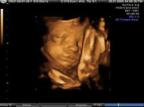

Los fetos bostezan en el útero

Un equipo de investigadores de las universidades de Durham y Lancaster (Reino Unido) sugiere que los fetos bostezan dentro del útero, un proceso de desarrollo que podría dar a los médicos otro índice de salud.